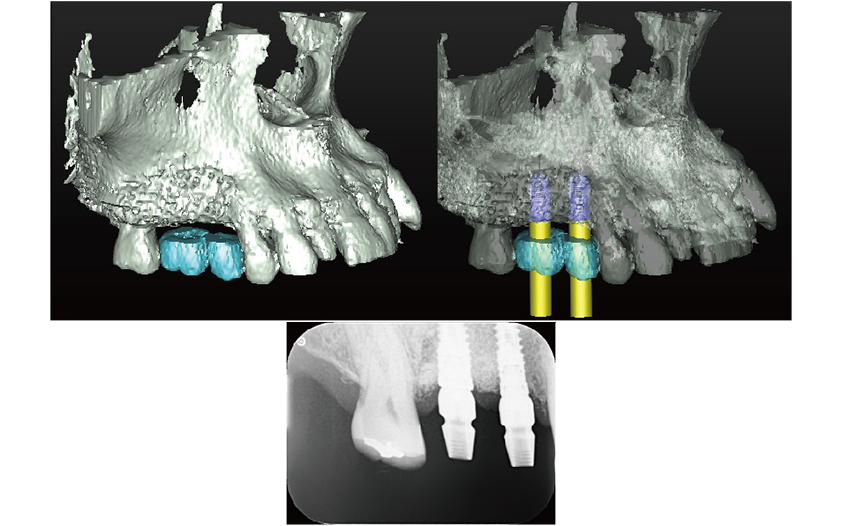

当院では安心安全なインプラント治療をより確実に行うために、すべてのインプラント治療で3Dコンピューターシミュレーションシステム「シンプラント プロ」で歯科CT画像からデータ解析を行い、サージガイドを作成するコンピューターガイデッド インプラント治療を行っています。

シンプラント プロのコンピューターガイデッド インプラント治療では、歯科CT画像から3D画像を構築し、骨の厚みや神経の走行などを視覚的に診査できます。

そして嚙み合わせ、骨の厚みや神経の走行からからみて三次元的に理想的なインプラントの位置を画像上でシミュレーションすることができます。これにより手術を行う前に安全で理想的なインプラントの位置を決定することが可能になりました。

画像は患者様に見てもらうことで予定するインプラントの施術後のイメージを画像で確認できます。

歯科CTデータからシンプラントで3D画像を表示して骨の厚みや神経、血管の走行を検査します

噛み合わせ、骨の厚みや神経の走行からみて理想的なインプラントの位置を決定

インプラント治療の仕上がりのイメージは画像で患者様も視覚的に確認できます

コンピューターガイデッド インプラント治療とは

「シンプラント プロ」で計画されたシミュレーションデータからサージガイドを作製します。

作製されたサージガイドをお口の中に装着して手術を行うことにより、計画した位置をお口の中に正確にトランスファーしてインプラント手術することができます。

サージガイドを使用することで、狭く小さいお口の中や手術しにくい奥歯でも精度の高い正確なインプラント治療が行うことが可能です

コンピューターガイデッド インプラント治療では、歯科医師の経験にプラスして手術の精度もよく、安心安全なインプラント治療をより確実に行うことができます。

理想的な位置に計画された3DデータからCAD/CAMで高精度なサージガイドを作ります

治療前のシミュレーション

施術前のレントゲン

サージガイドを使用することによって計画された位置に正確な施術が可能です

― 治療後 ―

計画した位置に正確に施術することで良好な審美結果が得られます

当院では歯科用CT撮影を行い、シンプラントプロで3D画像診査をすることで、顎の骨の状態を視覚的に精密に診査することができます。

顎の骨が痩せてしまっている場合は、骨造成手術(GBR)を行うことで骨が足りない場合でもインプラント治療が可能です。

顎の骨が痩せてしまってインプラント治療ができるだけの十分な骨がない

骨造成を行うことでインプラント治療が可能になります

シンプラントで診査し計画した位置に正確にインプラントを施術します

痩せてしまった顎の骨を再生することで、骨が少ない場所でもインプラント治療は可能です

新プラントプロで3次元的に分析を行い、インプラントを埋入する位置を決定し、サージガイドを作成します